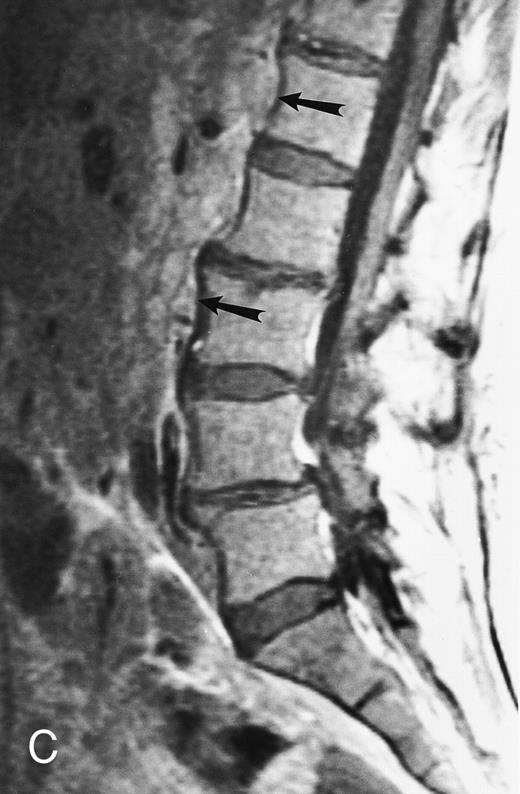

Focal MR pattern of abnormal marrow in a 48-year-old man with multiple myeloma: T1-weighted (500/10, TR/TE) (A), T2-weighted, fat-suppressed fast spin echo (5000/96, TR/TE, ET 16) (B), and enhanced T1-weighted (500/10, TR/TE) (C) sagittal MR images of the lumbar spine. Focal lesions (arrows) in L2 and S1 are dark in (A), bright in (B), and in (C) they enhance and become almost imperceptible from the uninvolved marrow.